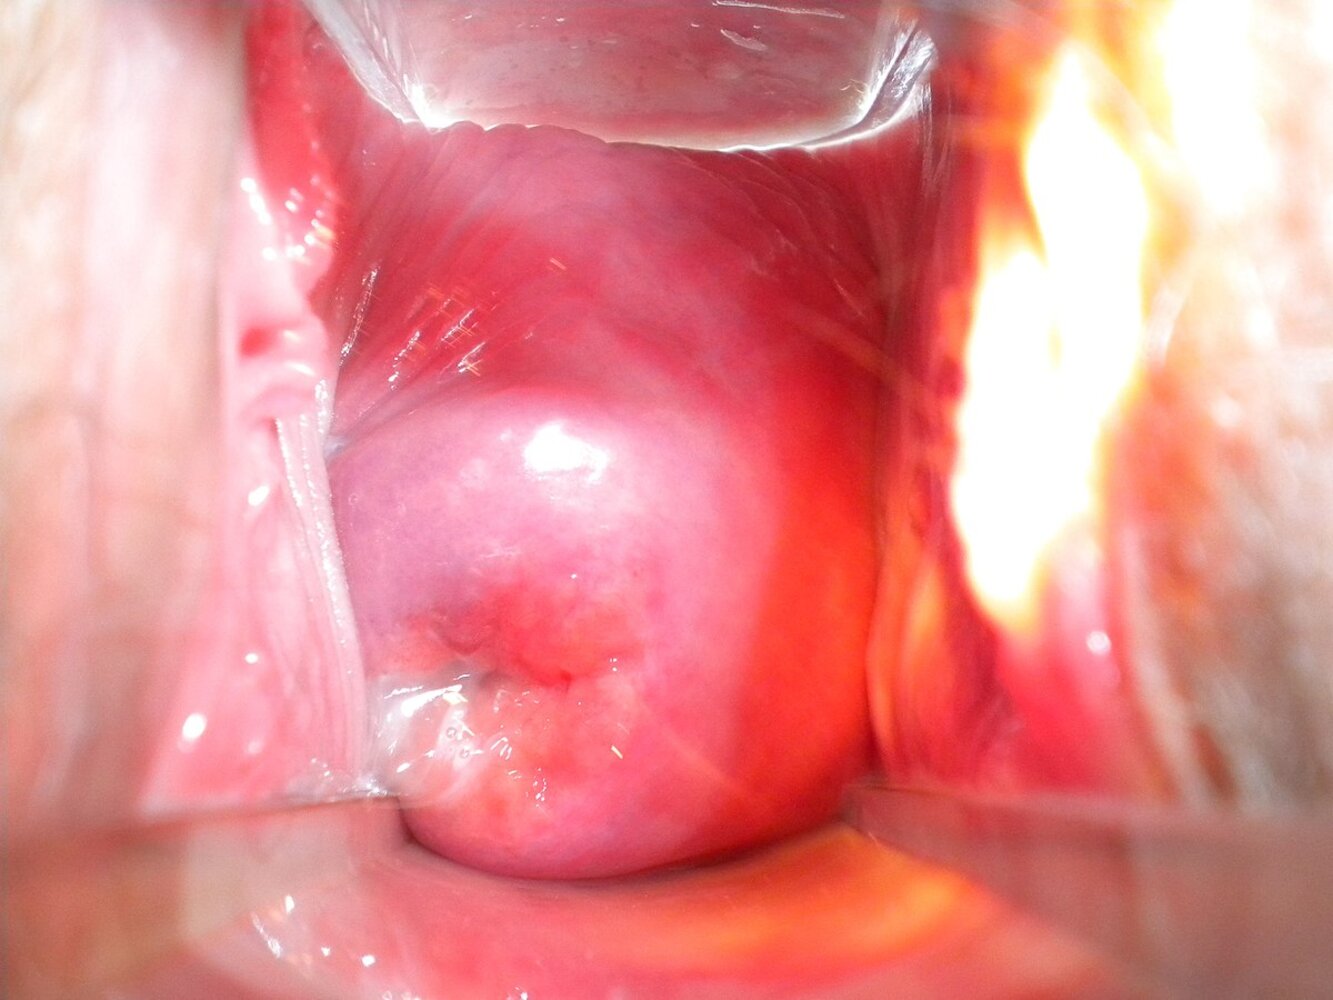

• Colposcope: a type of microscope used to acquire a magnified view of the ectocervix or vaginal wall

• Colposcopy: A diagnostic procedure to evaluate the cervix, vagina, and vulva using a colposcope; allows for assessment of the ectocervix under magnification (6–40 x)

• Application of acetic acid or iodine facilitates the colposcopic detection of precancerous and cancerous lesions

• Colposcopy-directed cervical smears and biopsies

• Surgical procedures under colposcopic guidance

Benign lesions

• No further evaluation necessary

• Cervical ectopy: a state in which the squamous cell epithelium of the ectocervix is replaced by columnar cell epithelium of the endocervix under the physiological influence of estrogen (e.g., pregnancy, certain oral contraceptives). Cervical ectopy is seen on colposcopy as a sharply demarcated bright red area with papillary structures.

• Clinical features: mostly asymptomatic; occasional postcoital bleeding and vaginal discharge

• Predisposition to chlamydial infection

• Malignant transformation may occur in cases of HPV-16 and/or HPV-18 infections.

• Transformation zone: the area between the non-keratinized squamous epithelium of the ectocervix and the columnar epithelium of the endocervix. The transformation zone is a common site for infections and dysplastic changes.

• Nabothian cysts: retention cysts that arise in the transformation zone . These cysts have no pathological significance.

• Cervical polyps: hyperplastic cervical epithelium

• Clinical features: vaginal bleeding

• Malignant degeneration is rare

• Treatment: surgical resection of the polyp and cauterization of the polyp's pedicle to prevent recurrence

Abnormal findings

• Require further evaluation

• White lesions under acetic acid application: condylomata acuminata

• White membrane that cannot be scraped off: cervical leukoplakia

• Punctate lesions or coarse mosaic pattern: cervical intraepithelial neoplasia

• Atypical vessels: cervical cancer